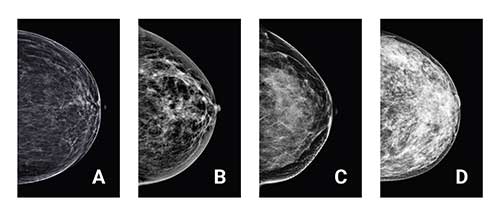

While all breasts are made up of fatty and fibrous or glandular tissue, not all breasts have the same combination of the two. When there is more fibrous/glandular tissue than fatty tissue, the breast is considered dense. Breast density is classified into one of four categories:

A.    Almost entirely fatty

B.    Scattered areas of fibroglandular density

C.    Heterogeneously dense

D.    Extremely dense

The last two categories are considered dense. And while dense breast tissue is completely normal, it does mean that additional imaging may be helpful to get a clearer picture of your breast cancer risk.